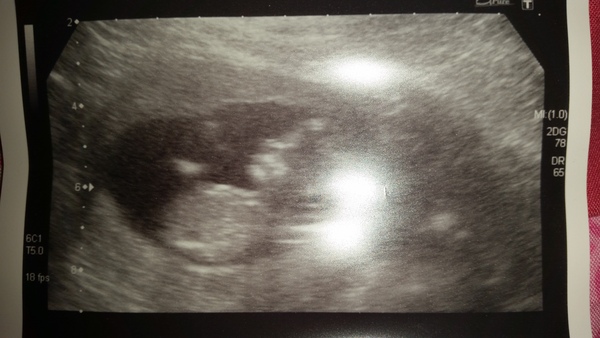

All good with baby today - measuring 12+3 so an amended due date of Friday 9th December. So incredibly relieved - Next milestone 16w and finally starting to tell people!

Lily that's wonderful news, the light on your scan photo makes me think of the sun shining on your baby.